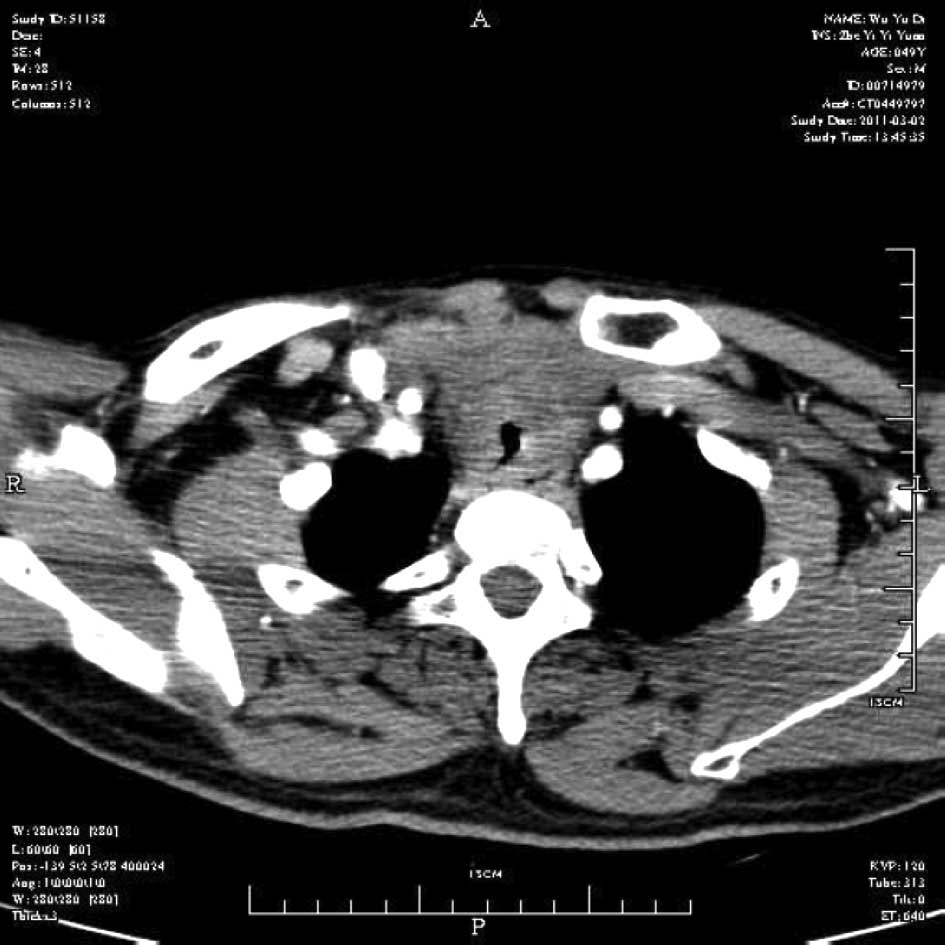

Emergency management of a patient with severe airway obstruction resulting from poorly differentiated thyroid carcinoma: A case report

We present a case of a life-threatening almost complete airway obstruction resulting from poorly differentiated thyroid carcinoma in a 48-year-old male. Airway obstruction may lead to unexpected mortality by suffocation and patients with poorly differentiated thyroid carcinoma usually have a fast deterioration and fatal outcome. In the case presented, we describe a safe and effective treatment strategy. Assisted by femoro-femoral cardiopulmonary bypass oxygenation, a tracheal stent was implanted successfully. Following surgery there were no complications, and chemoradiotherapy resulted in the relief of obstructing symptoms and improved the quality of life of the patient. This case indicates that femoro‑femoral cardiopulmonary bypass provides adequate oxygen support to undergo further management and that tracheal stent implant is an effective emergent measure to relieve severe airway obstruction in patients with poorly differentiated thyroid carcinoma.